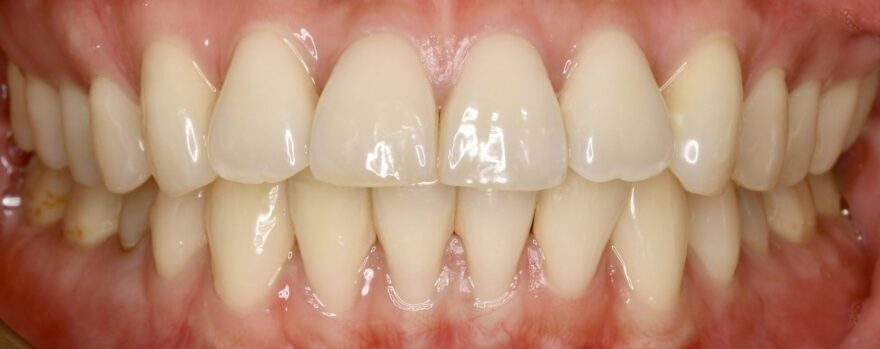

治療後の口腔内写真

約2年半の動的期間(歯を動かす時期)で、ここまで美しい歯並びになりました。

歯科矯正用アンカースクリュー無しだと、治療期間は更に1年長くなってしまったと思います。

前歯の捩れも無くなりました。